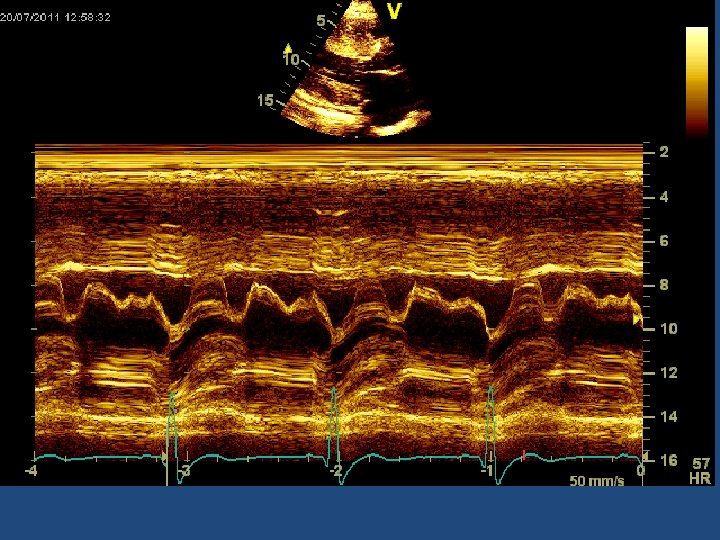

ECHO GRADING OF SAM